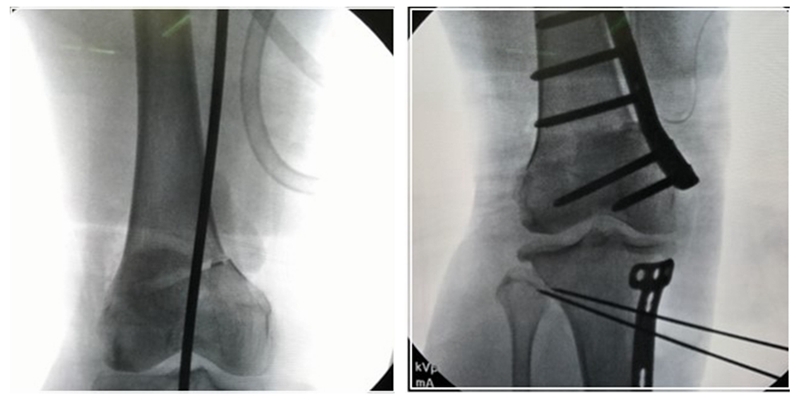

患者二,女性,膝外翻,膝外侧疼痛。通过做畸形分析后发现,该患者同时存在股骨侧畸形、胫骨侧畸形和关节内畸形(LDFA=82°,MPTA=104°,JLCA=6°)。

对于这类病人如何进行术前设计的关键点就在于目标力线应如何设计。要在骨性截骨的时候纠正骨性畸形,关节内畸形要通过关节内的方法解决。因为JLCA不平行,所以要同时画股骨侧关节线和胫骨侧关节线,并垂直于股骨侧关节线做出股骨侧目标力线,垂直于胫骨侧关节线做出胫骨侧目标力线。

根据各自目标力线,分别计算股骨内侧闭合和胫骨内侧闭合角度。

此患者股骨内侧闭合6°,经股内侧闭合13°。

术后影像